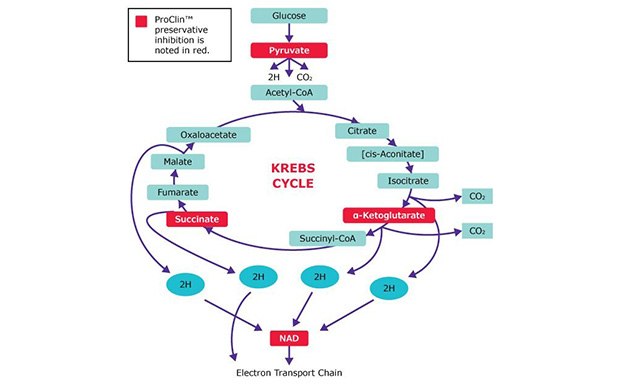

ProClin™ Preservatives

Discover ProClin™ preservatives: extend IVD reagent shelf life, inhibit microbes effectively, and ensure safety with no health or disposal concerns.